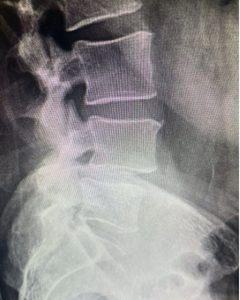

Image 2: The X-rays revealed that he had severe spinal stenosis as the L4 and L5 as well as spondylolisthesis, which caused instability.